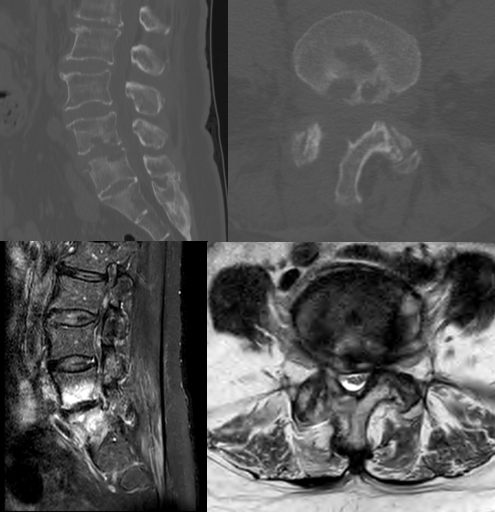

六、复发(2.27%)

病例(椎间盘突出复发)

女,42岁。

主诉:腰痛伴左下肢疼痛2月。

查体:疼痛放射至左侧臀部、大腿后侧、小腿后外侧。

思考和建议

完整切除突出的椎间盘

切除的椎间盘为影像学体积150%

视情况缝合纤维环,避免复发